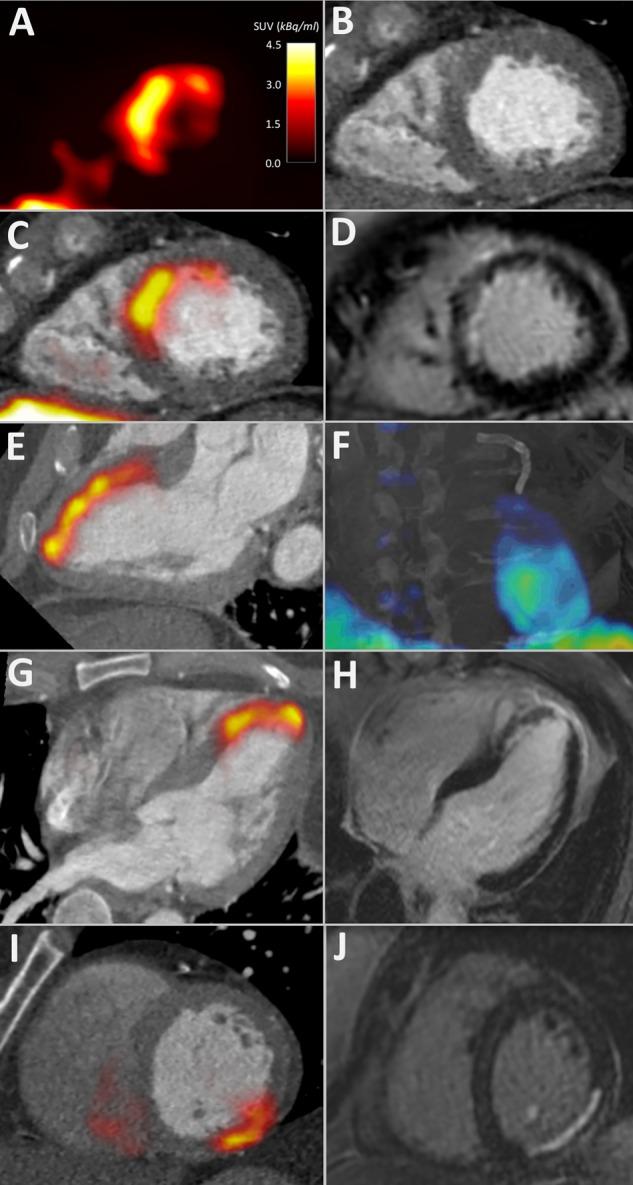

F-Fluciclatide (a novel αβ-selective radiotracer) positron emission tomography (PET) and CT imaging and gadolinium-enhanced MRI (CMR) were performed in 21 patients 2 weeks after ST-segment elevation MI (anterior, n=16; lateral, n=4; inferior, n=1). CMR was repeated 9 months after MI. 7 stable patients with chronic total occlusion (CTO) of a major coronary vessel and nine healthy volunteers underwent a single PET/CT and CMR.

F-Fluciclatide uptake was increased at sites of acute infarction compared with remote myocardium (tissue-to-background ratio (TBR) 1.34±0.22 vs 0.85±0.17; p<0.001) and myocardium of healthy volunteers (TBR 1.34±0.22 vs 0.70±0.03; p<0.001). There was no F-fluciclatide uptake at sites of established prior infarction in patients with CTO, with activity similar to the myocardium of healthy volunteers (TBR 0.71±0.06 vs 0.70±0.03, p=0.83). F-Fluciclatide uptake occurred at sites of regional wall hypokinesia (wall motion index≥1 vs 0; TBR 0.93±0.31 vs 0.80±0.26 respectively, p<0.001) and subendocardial infarction. Importantly, although there was no correlation with infarct size (r=0.03, p=0.90) or inflammation (C reactive protein, r=-0.20, p=0.38), F-fluciclatide uptake was increased in segments displaying functional recovery (TBR 0.95±0.33 vs 0.81±0.27, p=0.002) and associated with increase in probability of regional recovery.